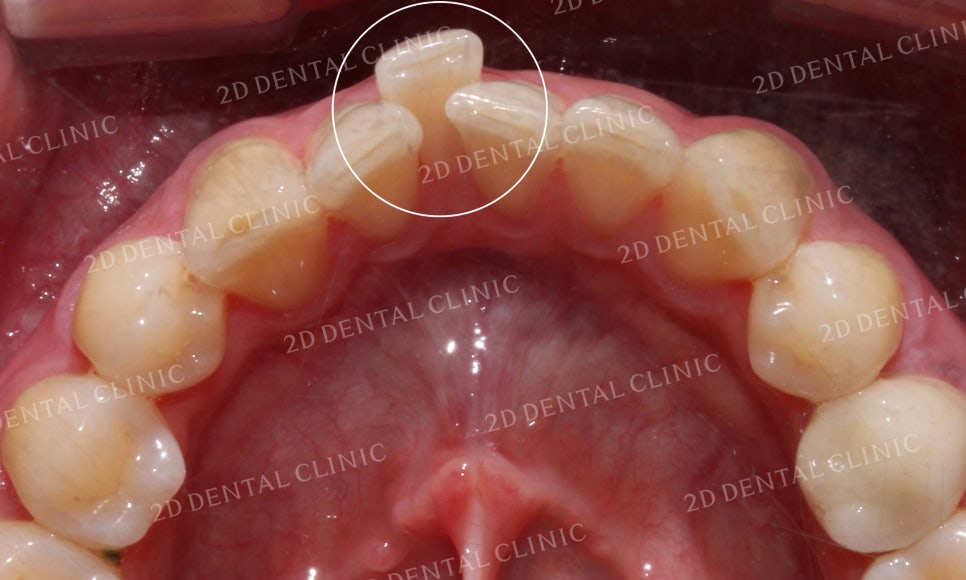

하악의 설측면 사진에서도

크라우딩으로 인해

전치부의 치아들이

삐뚤거리고 있습니다.

특히 중절치가 심하게

틀어져 있는 모습이네요.

하악의 설측면 역시 전치부가

총생으로 들쭉날쭉했었는데요,

교정 후 덧니처럼 틀어졌던 부분들이 사라지고

매끈하게 재배열된 치아를 확인할 수 있습니다!